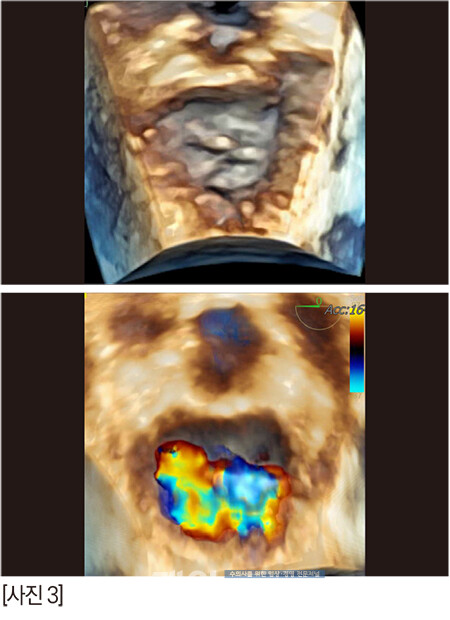

알박사가 ‘risk’라고 하면서 술자들에게 한번 더 주지시킨 이미지이다. 화살표들은 조심해야 하는 부분들 혹은 판막의 심한 퇴행성 변화를 의미하는 곳이다. 이렇게 되면 우리에게는 정답 zone은 딱 하나다.

판막을 가로지르는 저 화살표. 저 곳밖에는 답이 없다. 힘든 수술이 될 것이었다.